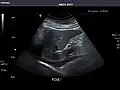

Liver

Ultrasonography of the liver with some standard measurements[6]

In patients with deranged liver function tests, ultrasound may show increased liver size (hepatomegaly), increased reflectiveness (which might, for example, indicate cholestasis), gallbladder or bile duct diseases, or a tumor in the liver.

Ultrasonography of liver tumors involves two stages: detection and characterization. Tumor detection is based on the performance of the method and should include morphometric information (three axes dimensions, volume) and topographic information (number, location specifying liver segment and lobe/lobes). The specification of these data is important for staging liver tumors and prognosis. Tumor characterization is a complex process based on a sum of criteria leading towards tumor nature definition. Often, other diagnostic procedures, especially interventional ones, are no longer necessary. Tumor characterization using the ultrasound method will be based on the following elements: consistency (solid, liquid, mixed), echogenicity, structure appearance (homogeneous or heterogeneous), delineation from adjacent liver parenchyma (capsular, imprecise), elasticity, posterior acoustic enhancement effect, the relation with neighboring organs or structures (displacement, invasion), vasculature (presence and characteristics on Doppler ultrasonography and contrast-enhanced ultrasound (CEUS).